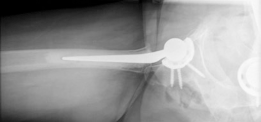

Standard antero-posterior and cross-table lateral radiographs of the pelvis and left hip were obtained immediately following the primary clinical assessment.

The initial AP pelvis radiograph clearly demonstrated a displaced left femoral neck fracture. The fracture line was entirely intracapsular. The femoral head was superiorly and posteriorly displaced relative to the femoral neck, with evidence of approximately 1.5 cm of shortening. The bone quality appeared reasonable for the patient's age, with a preserved Singh index and cortical thickness in the diaphyseal region, though some osteopenia was evident in the proximal trabecular patterns. No signs of pre-existing significant hip osteoarthritis (such as joint space narrowing, subchondral sclerosis, or osteophytosis) in the ipsilateral joint were noted. The contralateral hip appeared unremarkable.

Further radiographic views confirmed the complete displacement and the lack of cortical contact between the proximal and distal fragments. The fracture was classified as a Garden Type IV, indicating complete displacement with a loss of trabecular alignment between the femoral head and the acetabulum, where the head has rotated independently of the neck. Furthermore, it was classified as a Pauwels Type III, meaning the fracture line angle was greater than 70 degrees from the horizontal. This vertical fracture orientation indicates extremely high shear forces across the fracture site, portending a very poor prognosis for osteosynthesis and a high risk of nonunion or fixation failure if internal fixation were to be attempted.